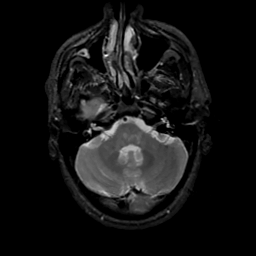

MR Study #16, June 23, 1991 -- Slice #11

[Home][Help][Clinical][Tour 1][Tour 2] Slice 11